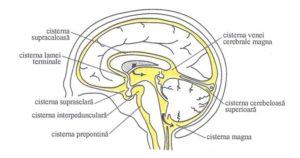

В местах, где субарахноидальное пространство естественным образом расширено, образуются мозговые цистерны, это значит, что основной объем циркулирующей цереброспинальной жидкости содержится в этих полостях. Подпаутинные цистерны – зоны естественного увеличения объема субарахноидального пространства, которые преимущественно находятся у основания мозга головы. Самые большие цистерны – базальная и затылочная.

Неравномерное расширение области субарахноидального пространства, расположенного в головном мозге, у взрослых пациентов встречается редко. Чаще патология выявляется у детей младенческого возраста. У новорожденных объем подпаутинной полости в норме меньше, чем у взрослого. Мозговые цистерны представляют собой часть сети, по которой осуществляется циркуляция цереброспинальной жидкости.

Цистерны – внешние резервуары, в то время как желудочки – внутренние. Если процессы продукции и резорбции (всасывание) ликвора уравновешивают друг друга, циркуляция поддерживается в нормальном режиме.

Размеры субарахноидального пространства в норме в 3 месяца не превышают 3 мм у доношенных младенцев, 4 мм – у недоношенных детей. Нормальные размеры мозговых цистерн составляют: большая цистерна, расположенная под мозжечком – до 10 мм (сагиттальный срез), цистерна четверохолмия – до 3 мм. Объем циркулирующего ликвора составляет около 120-140 мл.

Головной мозг человека окружают три защитные оболочки – твердая, паутинная и мягкая. Последняя непосредственно прилегает к мозговому веществу и обеспечивает его питание. Паутинная оболочка соединена с другими оболочками мозга с помощью соединительнотканных перепонок. В областях, где перепонки отсутствуют, находятся цистерны.